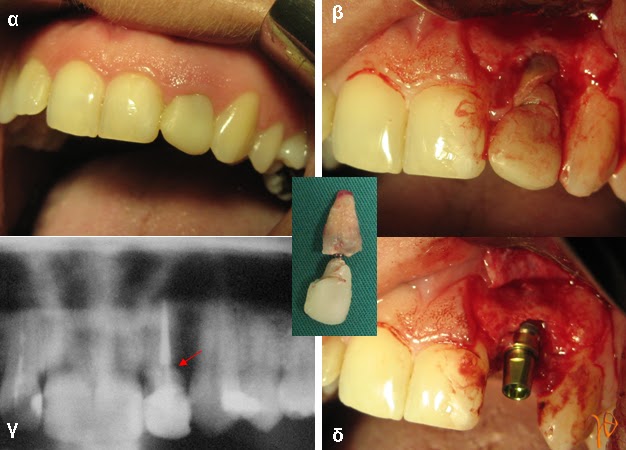

Περίπτωση 2: Άμεση τοποθέτηση οδοντικού εμφυτεύματος μετά από αφαίρεση του #22 που παρουσίαζε κάταγμα.

Εικόνα 2.1: (α) κλινική εικόνα, (β) το κάταγμα του #22, (γ) το κάταγμα του #22 στην πανοραμική ακτινογραφία (βέλη), (δ) τοποθέτηση οδοντικού εμφυτεύματος στη θέση του εξαχθέντος #22 (ένθετη φωτογραφία).>